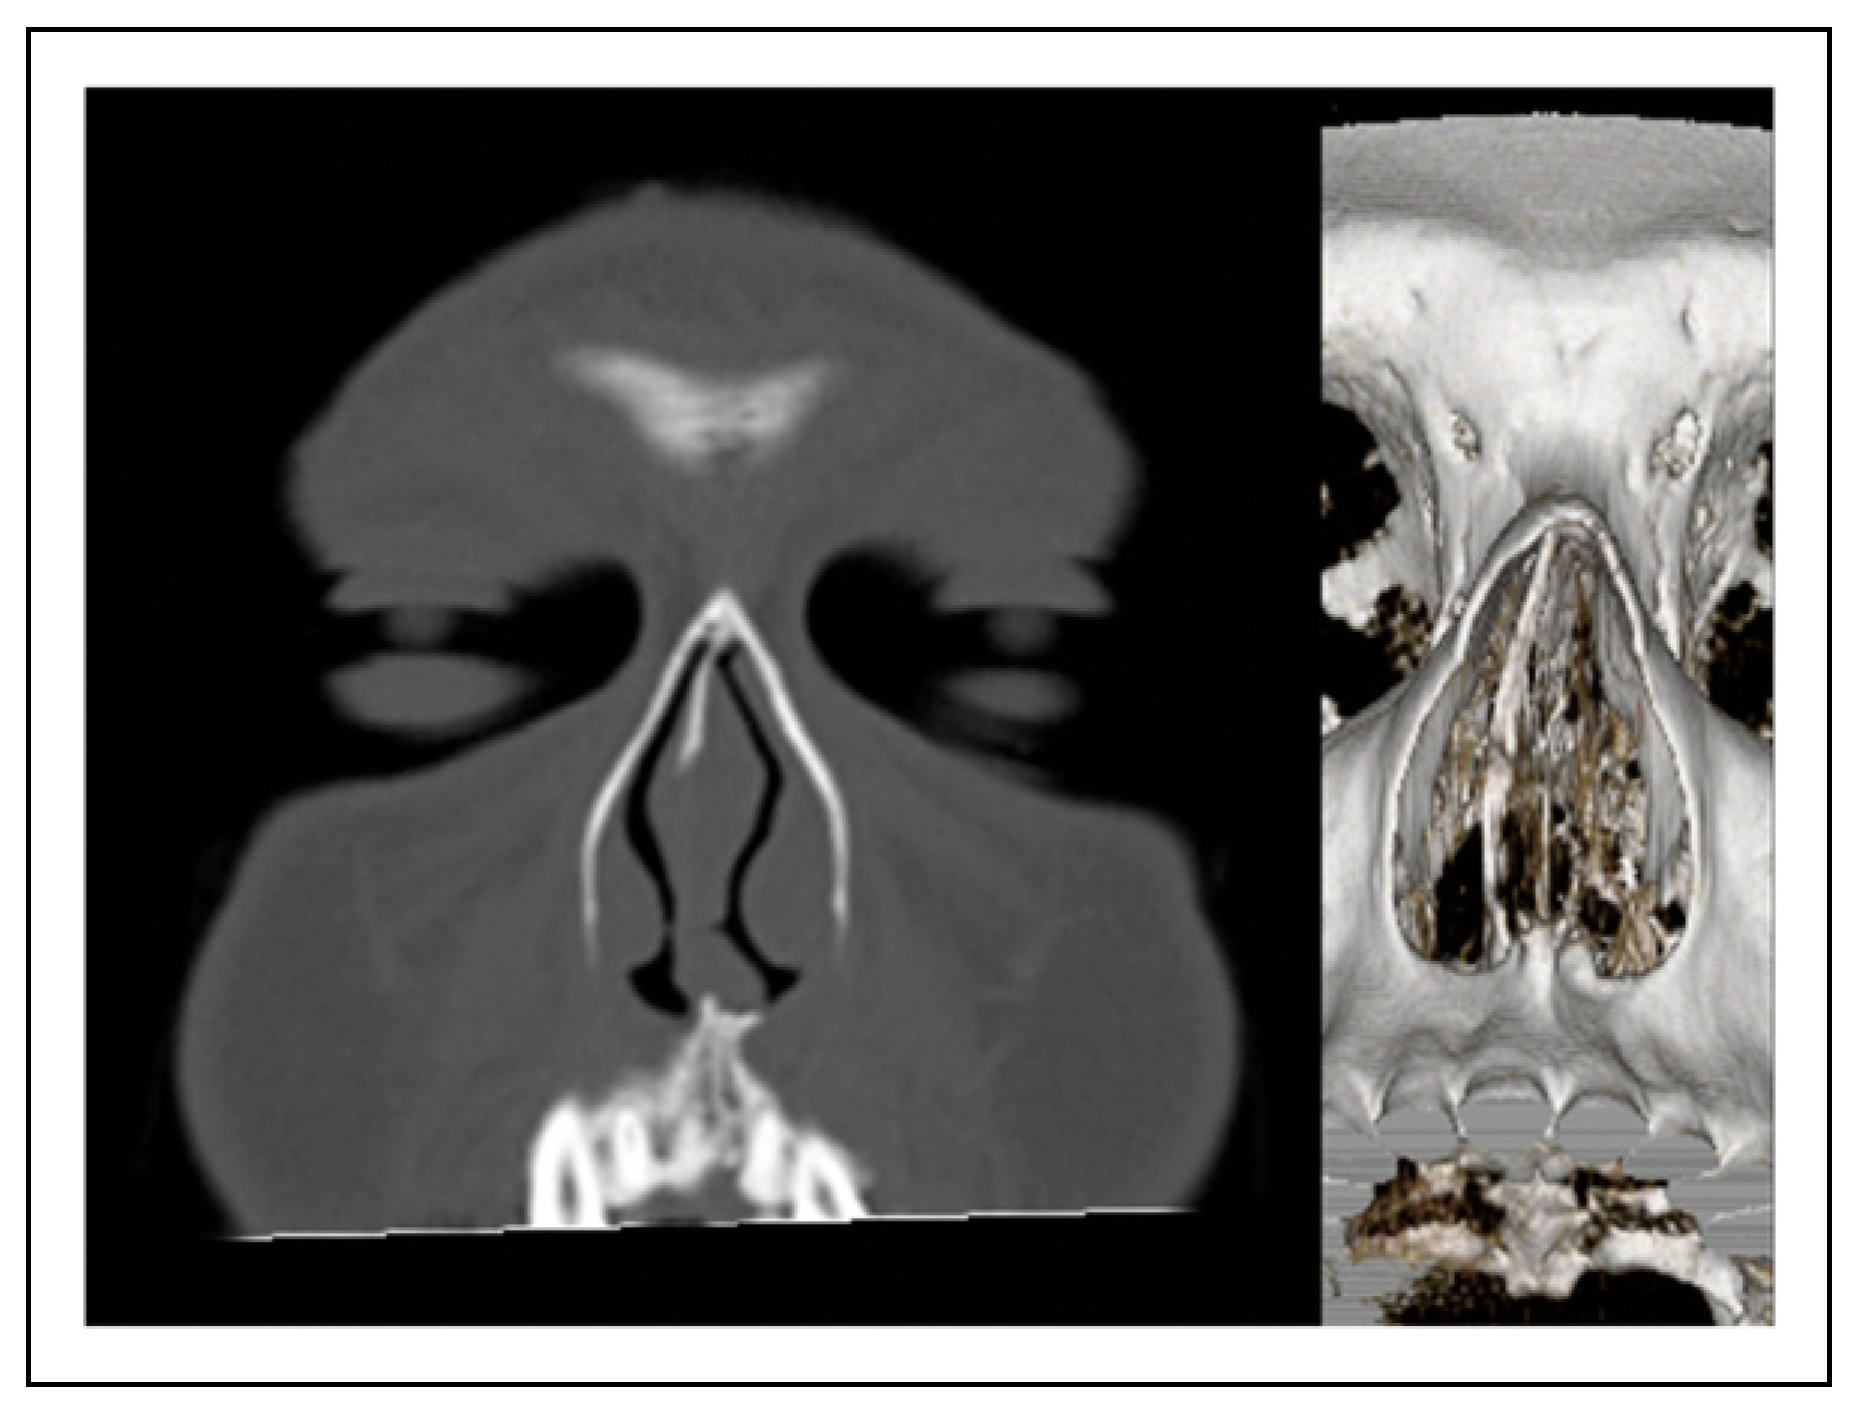

On examination, the septum showed caudal septal deviation to the left and moderate bilateral turbinate hypertrophy. A positive Cottle maneuver determined the presence of left nasal valve obstruction. Review of his pre-operative CT scan showed bilateral turbinate hypertrophy, deviations of the perpendicular plate of ethmoid, and a shifted ANS to the left side (Figure 1). The patient was scheduled for a functional rhinoplasty to relieve his nasal obstruction and correct the caudal septal deviation. The procedure was performed using a standard open rhinoplasty approach combined with anterior septal reconstruction and anterior nasal spine relocation. The patient was managed as an outpatient. Medications and wound care instructions were given. Intranasal Doyle splints, external taping, and nasal splits were left in place for 7 days post-operatively. Follow-up at 1 and 2 weeks confirmed a stable repair and improvement in nasal breathing.

Figure 1. Pre-operative CT showing deviated ANS.